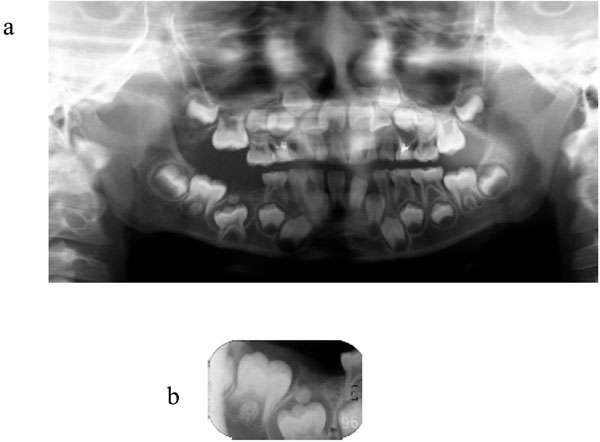

Одонтома нижней челюсти: фотографии и медицинская информация